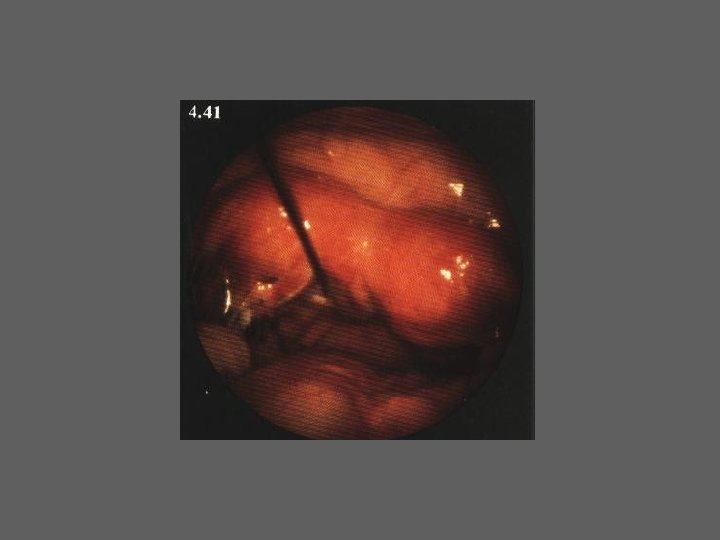

HISTEROSCOPIA - INDICAÇÕES Todas a situações em que se julgue vantajosa uma visualização completa da cavidade uterina, em particular: – Metrorragias – Dismenorreia adquirida – Infertilidade – Abortamentos de repetição e parto pré-termo – HSG anormal – DIU “perdido” – GIFT e ZIFT – Tratamento cirúrgico da patologia intracavitária: ● pólipos, miomas, septos, sinéquias, recessões endometriais ● baixos custos, reduzida morbilidade